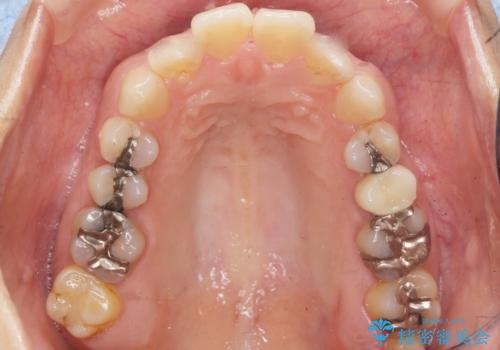

根管治療により症状がなくなり、またセラミッククラウンの自然な仕上がりにご満足頂けました。

クラウンの種類:オールセラミッククラウン スタンダード